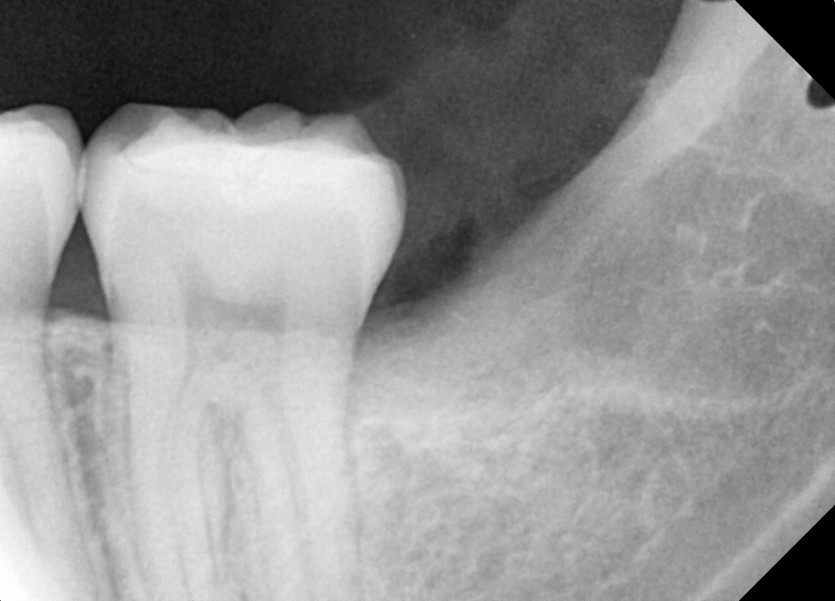

#38 사랑니 발치

구강 외과 전문의가 당일 발치했습니다.